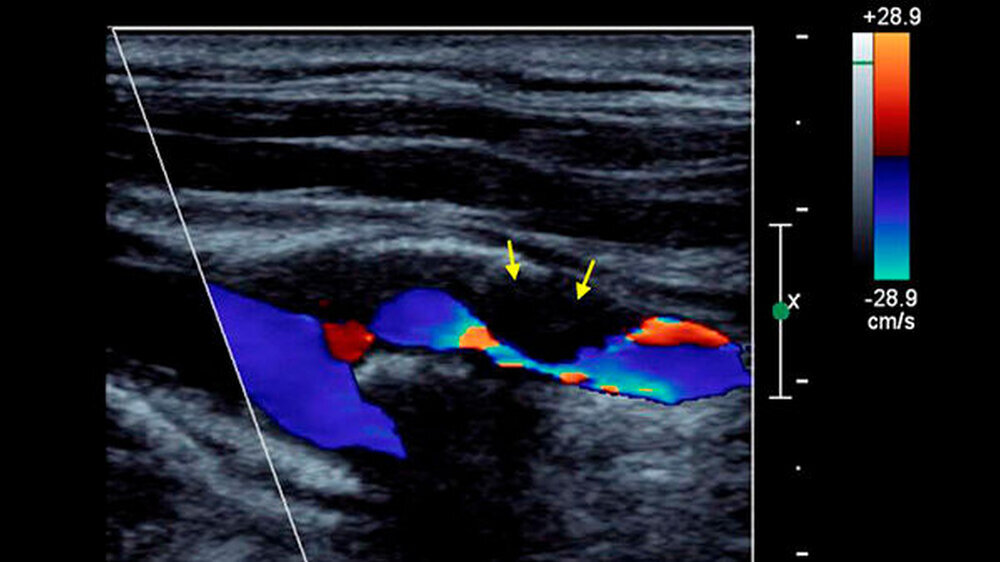

Wie gut diese Umgehungswege der Blutversorgung beim einzelnen Menschen funktionieren, kann durch den Ultraschalltest erfasst werden. Dabei wird gemessen, ob trotz der Gefäßverengung im Kopf noch eine ausreichende Durchblutungsreserve besteht. Diese Reserve wird beispielsweise durch das Anhalten des Atems für 30 Sekunden bei gleichzeitiger Ultraschallmessung der Hirngefäße bestimmt. Durch das Anhalten des Atems steigt der Kohlenstoffdioxidgehalt im Blut an.

Bei einer vorhandenen Reserve führt das zu einer Erweiterung der Hirngefäße und Zunahme der Durchblutung im Gehirn - ein sicheres Zeichen dafür, dass der Gefäßverschluss im Gehirn gut ausgeglichen wird. Andere Methoden zur Risikobestimmung bei Carotis-Stenose befassen sich mit dem Aufbau der Arterienverengung (Plaque) im Ultraschall oder der Kernspintomografie. Hier fehlen aber noch groß angelegte Untersuchungen. Ferner können mittels Ultraschall kleine Gerinnsel, die sich von der Plaque ablösen, erfasst werden (Mikroemboli-Detektion).